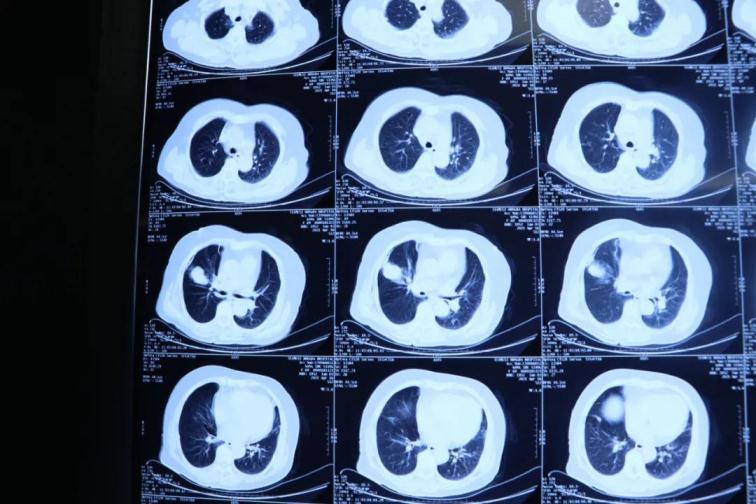

為了提高CT影像下肺腫瘤定位的精準(zhǔn)度,術(shù)前胸外科團隊聯(lián)合CT影像科趙文禮主任和董明鑫醫(yī)師詳細(xì)研究了肺CT定位方案,采取國際上先進的CT網(wǎng)格定位法,對肺腫瘤精確定位,定位精度可達(dá)5mm以內(nèi)。經(jīng)過團隊合作充分準(zhǔn)備后對肺癌實施了氬氦刀穿刺治療,微創(chuàng)穿刺針孔3mm,局麻鎮(zhèn)痛,分段治療40分鐘。病人全程在韋文康護士長護理團隊心肺監(jiān)測下進行,確保了手術(shù)安全。

氬氦刀治療后即刻CT評價肺腫瘤核心密度下降,手術(shù)后5天CT評價肺癌與周圍正常肺組織對比,水腫帶形成,癌組織出現(xiàn)壞死。治療取得了良好效果。遠(yuǎn)期效果需要繼續(xù)隨訪觀察。病人手術(shù)后1周無并發(fā)癥痊愈出院。